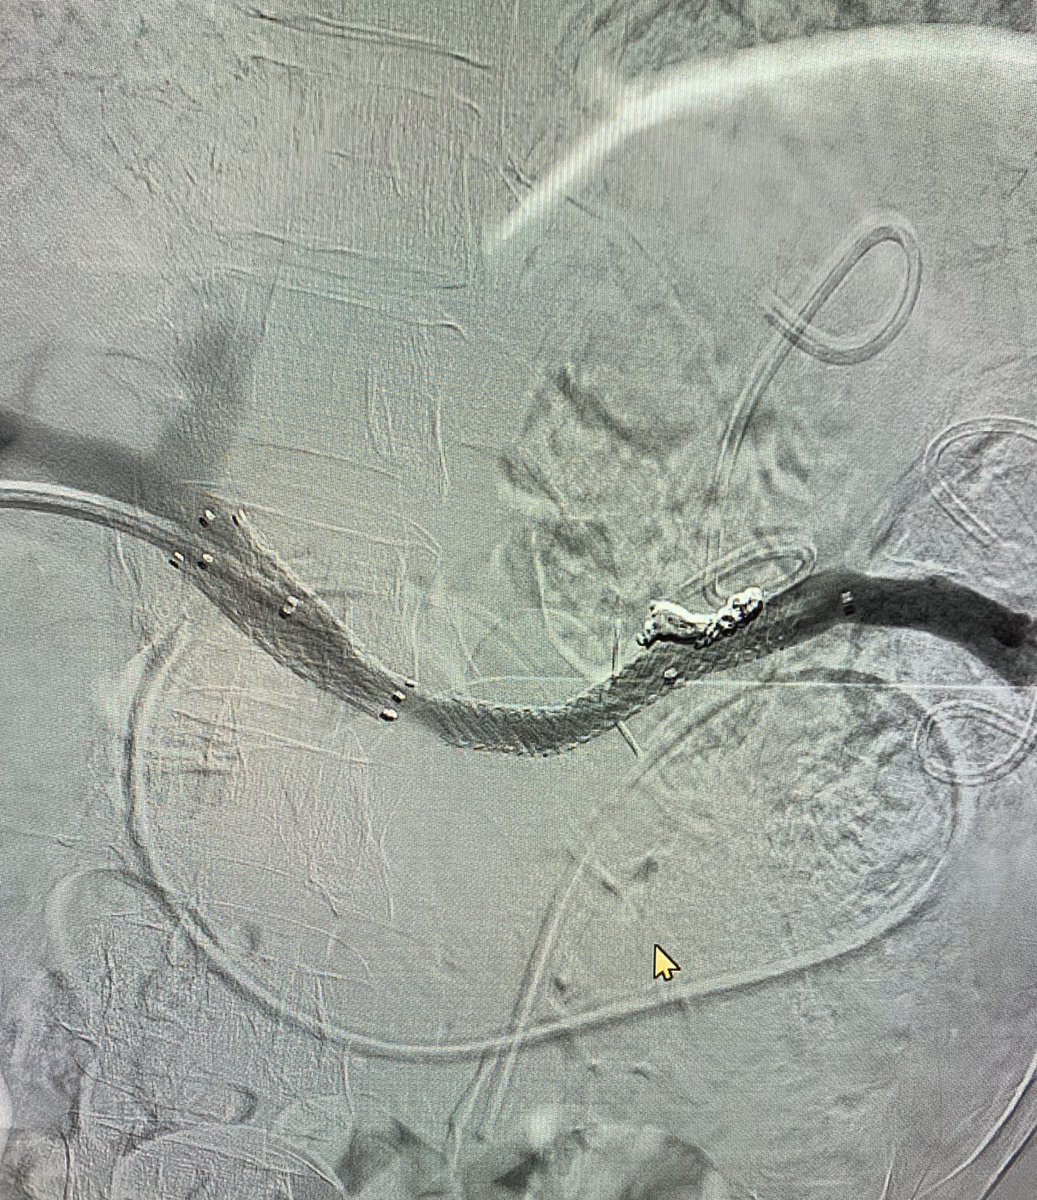

Last case of 2019. Successful

#recanalisation of chronic#splenicvein#occlusion using#transhepatic approach.#portalvein and#SMV reconstructed for#palliation#pancreaticcancer. Wish everyone happy 2020.#irad@SIRspecialists@SIR_ECS@SIRRFS@JVIRmedia@CVIR_Journalpic.twitter.com/Lgma0lTJUd